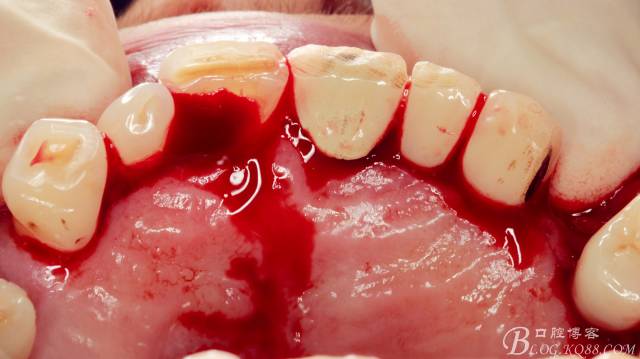

局麻下做齦溝內(nèi)切口

翻瓣,長柄球鉆清掃薄薄的骨皮質(zhì),暴露出牙冠,動作一定要輕柔,感覺就像在雞毛撣子一樣撣花瓶上的灰一樣,因?yàn)楣呛脱烙再|(zhì)有明顯的密度差異,手感上面差別比較明顯。